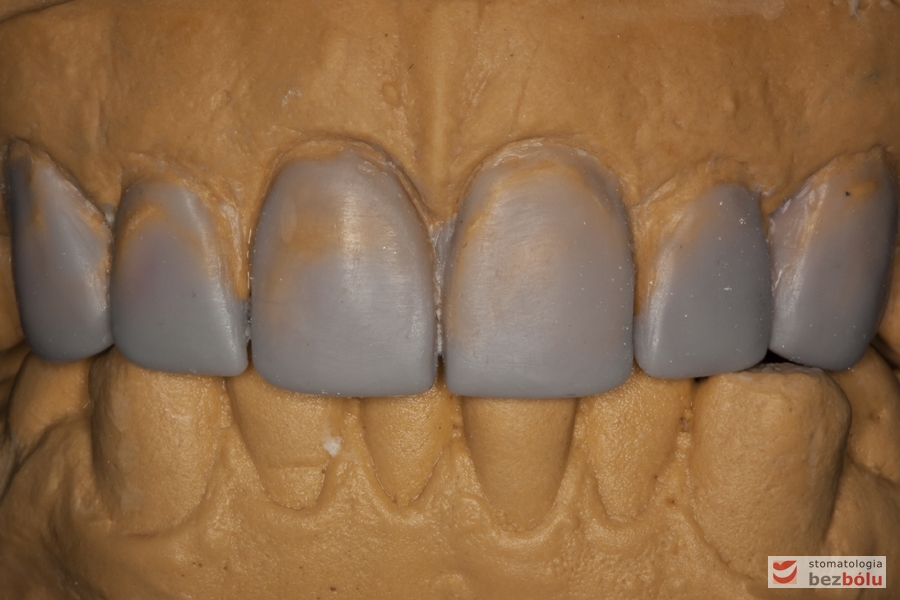

Modele gipsowe w artykulatorze - nawoskowane zęby od kła do kła w celu ich wydłużenia

Modele gipsowe w artykulatorze – nawoskowane zęby od kła do kła w celu ich wydłużenia